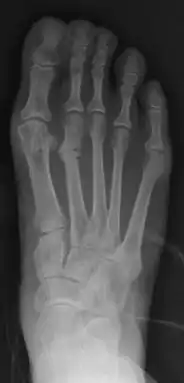

Primus varus deformity is the leaning of the first metatarsal bone away from the second metatarsal and towards the opposite foot (Fig. 1). As it leans over, its head sticks out to form the bunion bump and it also widens the forefoot to cause shoes feeling too tight. Thus when bunion pain becomes unmanageable, surgical correction is to narrow the forefoot by repositioning of the first metatarsal head back to its normal position. This can be done by osteotomy (bone-breaking), soft tissue (non-osteotomy) or fusion techniques.

- For recurrence correction after osteotomy procedure (Fig. 8)

Late deformity recurrence can happen after osteotomy (bone-breaking) procedures because osteotomy surgeries do not specifically stabilize first metatarsal bone.